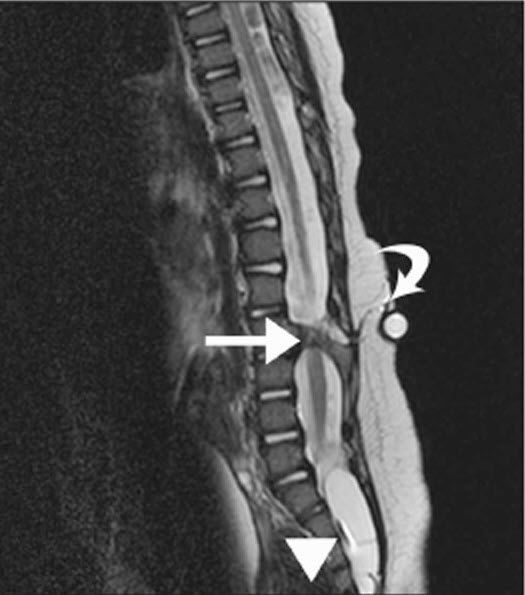

Diastematomyelia is a disease of spinal cord which belongs to a class of diseases called spinal dysraphism. Spinal dysraphism is refers to any tissue abnormality thar disrupt normal function and structure of spine or spinal cord. Diastematomyelia is also known as split spinal cord. It is characterized by presence of a sagittal cleft that divides the spinal cord into two parts. Reference: Bailey and Love's Short Practice of Surgery Image via: https://boneandspine.com/wp-content/uploads/2017/10/diastematomyelia.jpg